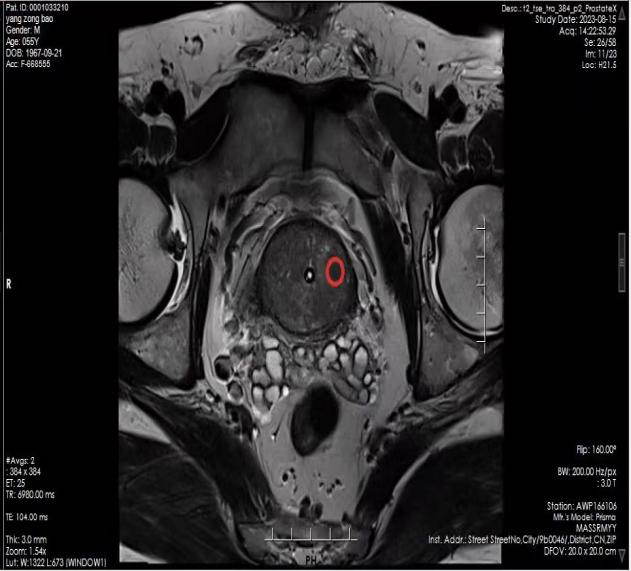

超聲介入團隊聯(lián)合影像科為患者進行前列腺融合導航穿刺

患者楊先生因前列腺特異性抗原(PSA/TPSA)升高伴前列腺體積增大等癥狀就診。入院后,泌尿外科醫(yī)師根據(jù)患者臨床癥狀和實驗室檢查,判斷需行穿刺活檢術以明確診斷,遂向超聲醫(yī)學科發(fā)出穿刺申請,并完善了穿刺術前各項檢查檢驗。超聲醫(yī)學科介入團隊接到穿刺申請后,對患者做出全面評估,與影像科聯(lián)絡,調取磁共振影像,為患者制定了超聲-磁共振融合導航下經(jīng)會陰穿刺的診斷方案。在科副主任兼介入組長劉丹丹的指導下,超聲介入科、影像科醫(yī)生為患者精確開展超聲-磁共振融合導航下經(jīng)會陰前列腺穿刺活檢術。術中在嚴密觀測患者各項生命體征下,醫(yī)生團隊精準進行靶區(qū)穿刺,術畢給予止血、抗感染處理,并進行及時的術后病理隨訪。

超聲-磁共振融合導航技術的原理是利用磁共振對于前列腺診斷的高度敏感性和特異性,經(jīng)過軟件融合超聲實時引導準確定位,在病灶部位豎起“靶子”,特別是對于一些較“刁鉆”的位置,極大地提高了穿刺精確度與穿刺檢出率。與傳統(tǒng)穿刺相比,具有精準、安全、檢出率高、不需術前腸道準備、穿刺針數(shù)少(傳統(tǒng)穿刺需要穿刺8-13針)等優(yōu)勢。該項新技術的開展有助于前列腺癌的早診斷、早治療,減少穿刺相關的并發(fā)癥,提高根治率和患者的生存率。

融合導航術中超聲圖像